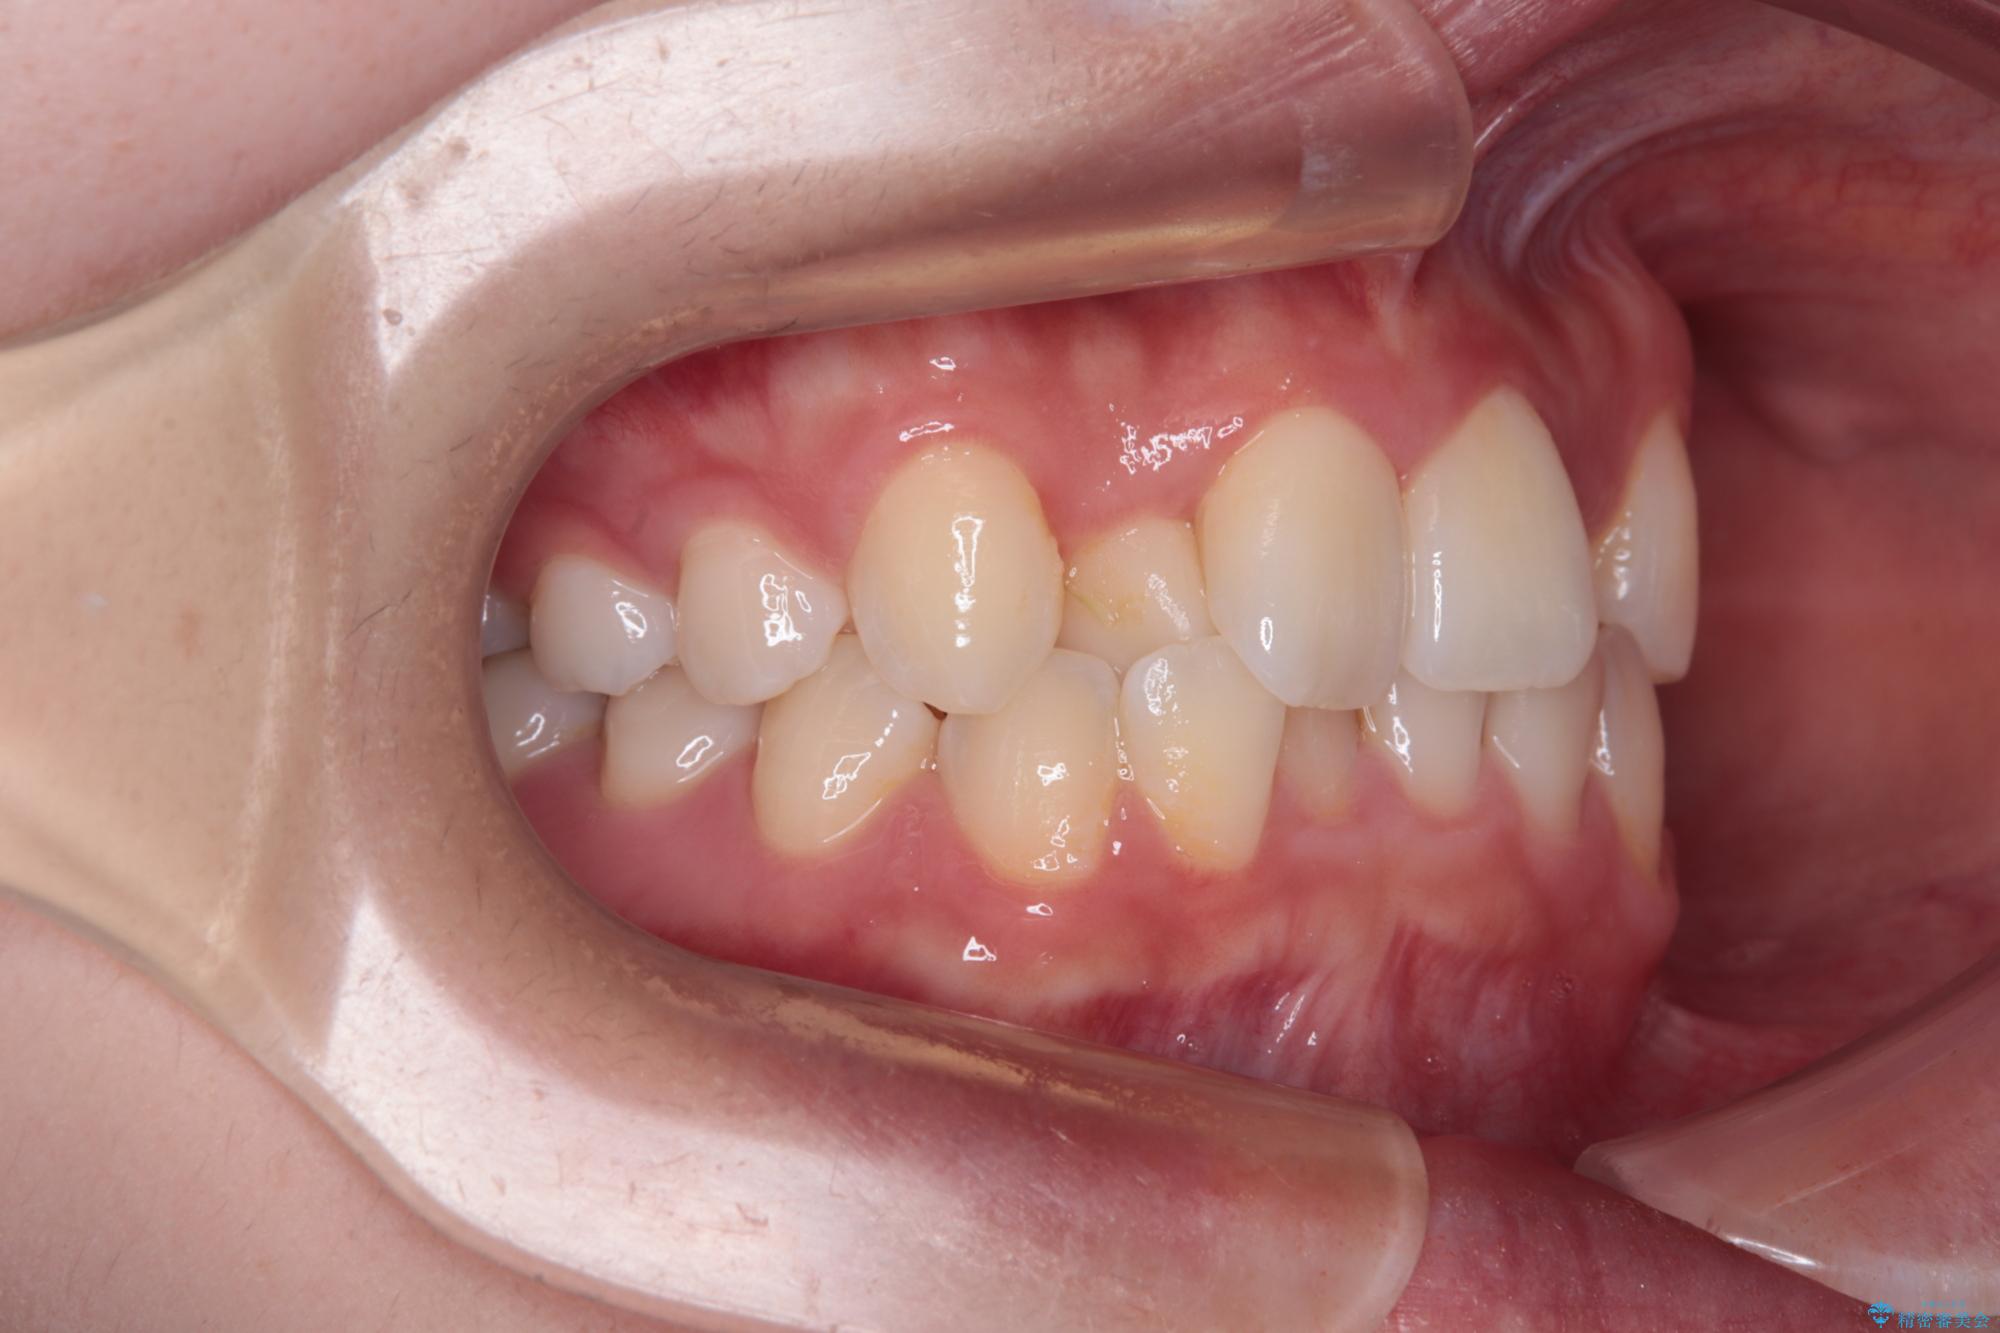

- 上顎前歯のクロスバイトを気にして来院された患者様です。

ワイヤー矯正でもマウスピース矯正でも対応可能でしたが、マウスピースによる自己管理に一切の自信がないとのことで、ワイヤー装置にて矯正治療を行うこととしました。